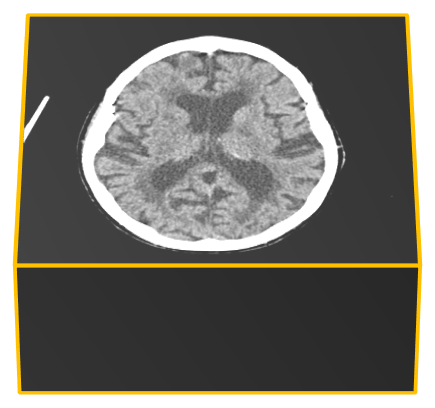

We present an effective method for Intracranial Hemorrhage Detection (IHD) which exceeds the performance of the winner solution in RSNA-IHD competition (2019). Meanwhile, our model only takes quarter parameters and ten percent FLOPs compared to the winner's solution. The IHD task needs to predict the hemorrhage category of each slice for the input brain CT. We review the top-5 solutions for the IHD competition held by the Radiological Society of North America(RSNA) in 2019. Nearly all the top solutions rely on 2D convolutional networks and sequential models (Bidirectional GRU or LSTM) to extract intra-slice and inter-slice features, respectively. All the top solutions enhance the performance by leveraging the model ensemble, and the model number varies from 7 to 31. In the past years, since much progress has been made in the computer vision regime especially Transformer-based models, we introduce the Transformer-based techniques to extract the features in both intra-slice and inter-slice views for IHD tasks. Additionally, a semi-supervised method is embedded into our workflow to further improve the performance. The code is available in the manuscript.

翻译:我们在RSNA-IHD竞争(2019年)中提出了一种有效的内爆出血检测方法(IHD),该方法超过了获胜者解决方案的绩效(RSNA-IHD 竞争(2019年),同时,我们的模型与获胜者解决方案相比,仅需要四分之一参数和10%的FLOP;国际HD的任务需要预测输入大脑CT的每个切片的出血类别。我们审查了北美辐射协会(RSNA)在2019年举办的IHD竞赛的5级顶级解决方案。几乎所有顶级解决方案都依靠2D共流网络和相继模型(双向GRU或LSTM)来提取虱内和肺间特征。所有顶级解决方案都通过利用模型共性能提高性能,而在过去几年中,模型数从7到31不等。由于计算机视觉系统,特别是以变压器为基础的模型取得了很大进展,因此我们采用了基于变压器的技术来提取IHDD任务的内切和相间观点的特征。此外,半超式方法已经嵌入我们的工作流程。